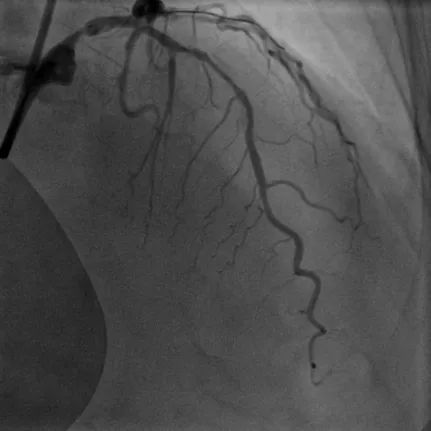

病例1

LAD长弥漫钙化病变:患者70岁男性,因间断胸痛3天入院,既往高血压病史、长期吸烟史,诊断不稳定型心绞痛。冠脉造影显示前降支近中段弥漫性狭窄伴钙化,应用冠脉腔内影像学技术-IVUS对该血管进一步评估,结果显示:前降支多处180-270°钙化,中段钙化结节(红色箭头所示)。顺利送入3.0*12mm Shockwave冲击波球囊至LAD中段,充盈4atm使球囊充分贴壁,显示球囊近段膨胀不良,随着冲击波能量释放,球囊逐渐扩张,膨胀扩张满意。先后对LAD多处钙化病变进行8个周期(80次脉冲)预处理,应用IVUS评估显示钙化处出现钙化断裂。该患者多处弥漫钙化病变,在IVUS指导下联合Shockwave冲击波球囊实现精准预处理,为后续支架植入奠定了基础。果然,送入长支架通过病变顺畅,释放扩张未感觉明显阻力即到位,支架膨胀舒展,成功植入支架。IVUS结果显示支架膨胀贴壁良好。

术前冠脉造影